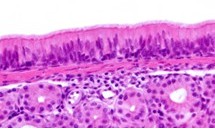

Fisiologia della clearance mucociliare

La mucosa respiratoria è costituita da cellule ciliate, cellule mucipare e cellule basali. Il muco intrappola particelle e patogeni mentre il movimento delle ciglia trasporta le secrezioni verso il rinofaringe. Alterazioni della viscosità del muco o del battito ciliare determinano ristagno secretivo e aumentano il rischio infettivo. [2]